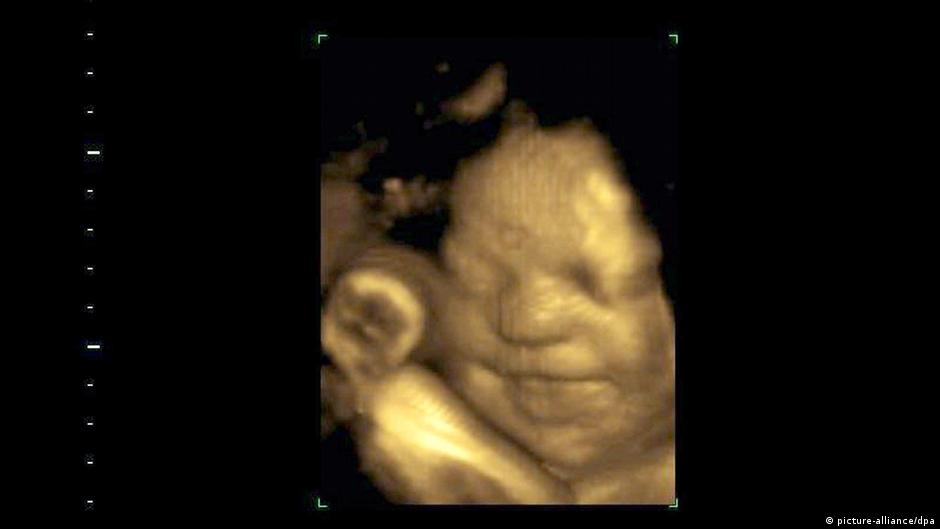

गर्भ में भी बच्चों के चेहरे गाजर के स्वाद से खिल उठते हैं

नई दिल्ली, 22 सितंबर। उत्तरपूर्वी इंग्लैंड में दुरहम यूनिवर्सिटी के रिसर्चरों का कहना है कि उनकी खोज से पहली बार इस बात के सीधे सबूत मिले हैं कि बच्चे जन्म से पहले ही अलग गंध और स्वाद को लेकर अलग तरह की प्रतिक्रिया देते हैं. वैज्ञानिकों की एक टीम ने 100 गर्भवती महिलाओं के 4डी अल्ट्रासाउंड स्कैन का अध्ययन किया और यह पता लगाया कि गाजर के स्वाद के संपर्क में आने वाले बच्चों के चेहरे पर हंसी दिखाई पड़ी. इसी तरह जिन बच्चों को गहरे रंग वाली पत्तेदार गोभी का जायका मिला उनके चेहरे रुआंसे हो गये.